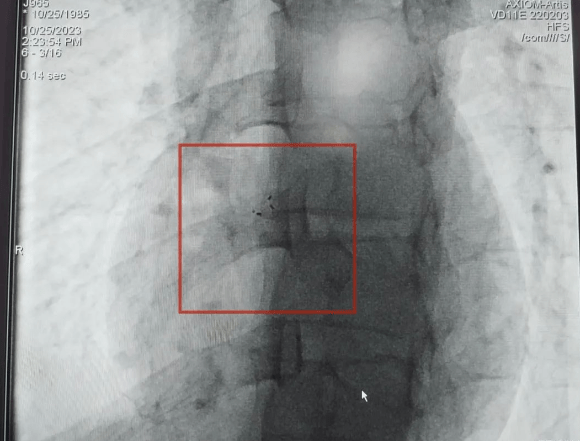

手術進行中

植入體內的封堵器

整個手術過程順利,術后患者頭昏明顯減輕,觀察24小時后即可出院。